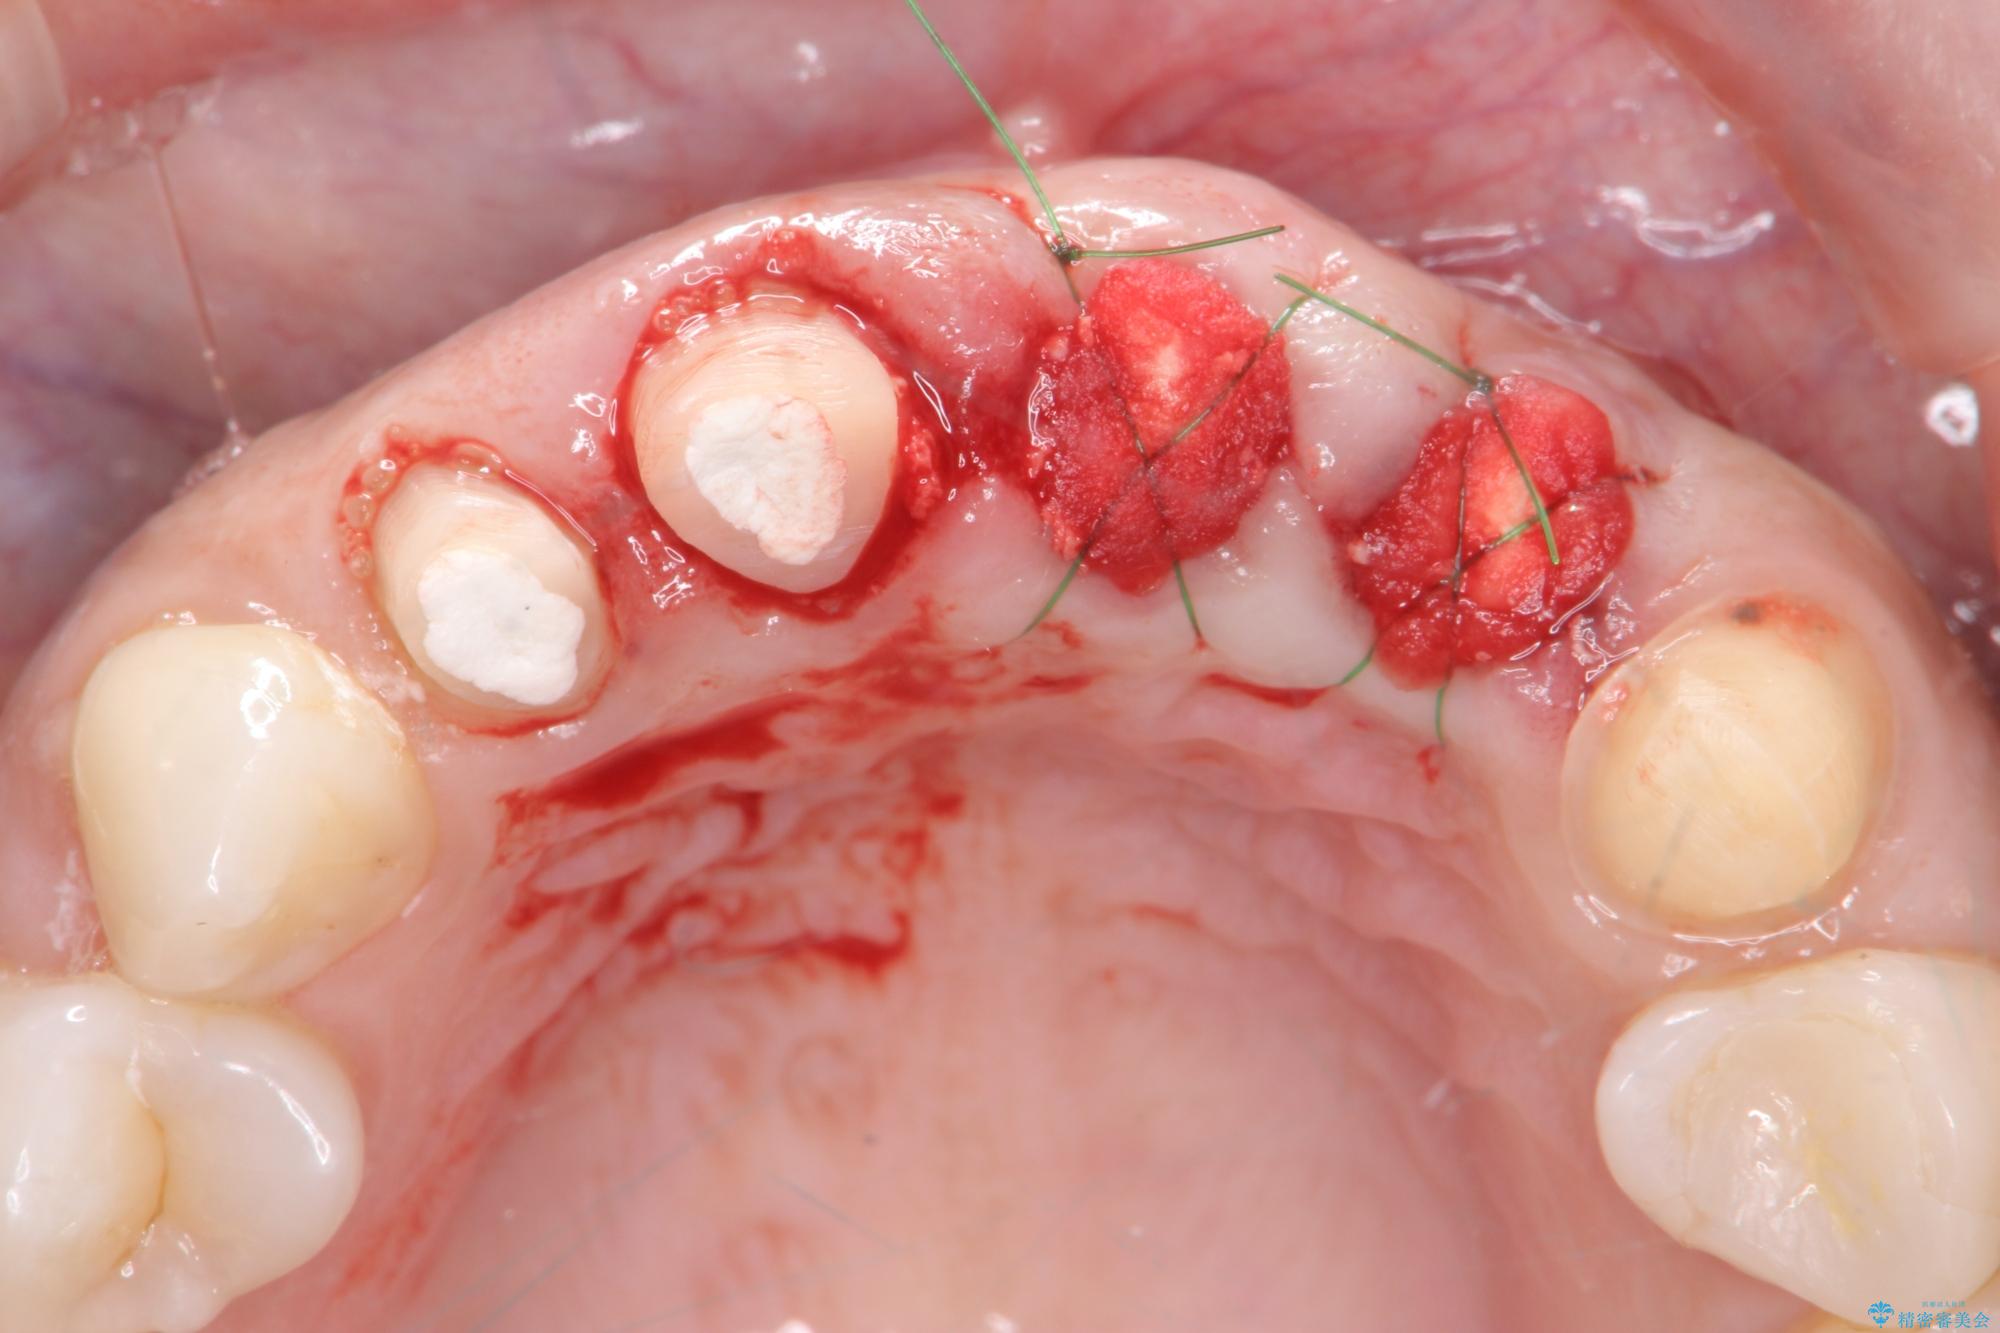

抜歯時に可及的に歯肉のボリュームを保つよう骨充填材とコラーゲン製剤による填塞を行い審美的かつ機能的なブリッジとなるよう治療を進めます。

治療中

歯槽堤保存術を併用したブリッジ治療 治療中画像 歯槽堤保存術を併用したブリッジ治療 治療中画像 歯槽堤保存術を併用したブリッジ治療 治療中画像 歯槽堤保存術を併用したブリッジ治療 治療中画像 歯槽堤保存術を併用したブリッジ治療 治療中画像 歯槽堤保存術を併用したブリッジ治療 治療中画像 歯槽堤保存術を併用したブリッジ治療 治療中画像